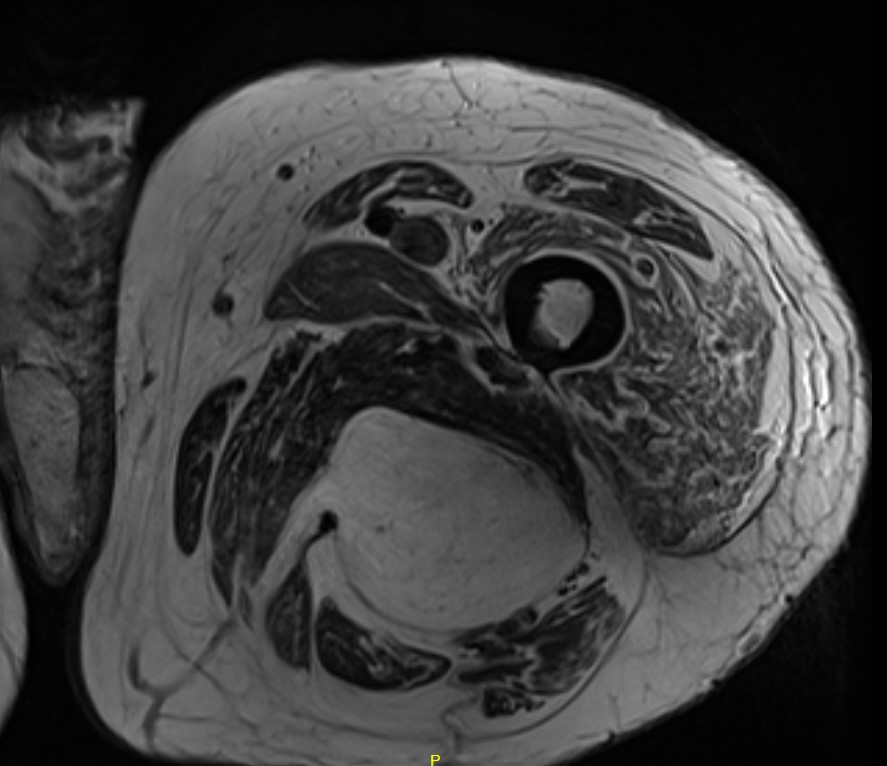

Liposarcoma posterior thigh

LS 3LS 2LS 1